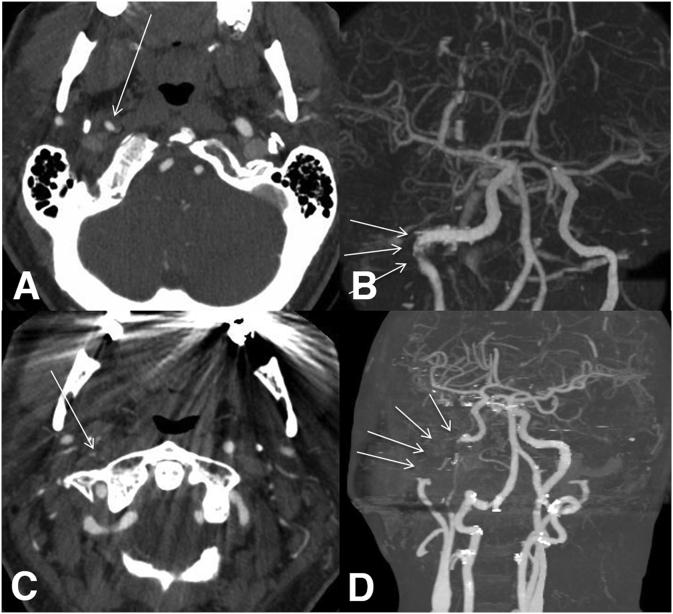

A patient whose initial neuro-ophthalmic manifestation was Horner syndrome, but who evolved over 14 days to display transient monocular vision loss, ipsilateral ocular ischemic syndrome, and episodic contralateral hemiparesis. Digital subtraction angiography demonstrated progressive ipsilateral carotid occlusion with lack of collateral flow. The patient underwent stenting with rapid reversal of transient monocular visual loss and hemiparesis. Follow-up examination several months later confirmed complete resolution of all clinical abnormalities.

一名患者最初的神经眼科表现为霍纳综合征,但在14天内病情进展,出现短暂性单眼视力丧失、同侧眼部缺血综合征和发作性对侧偏瘫。数字减影血管造影显示同侧颈动脉逐渐闭塞且无侧支血流。该患者接受了支架置入术,短暂性单眼视力丧失和偏瘫迅速逆转。数月后的随访检查证实所有临床异常均已完全消失。